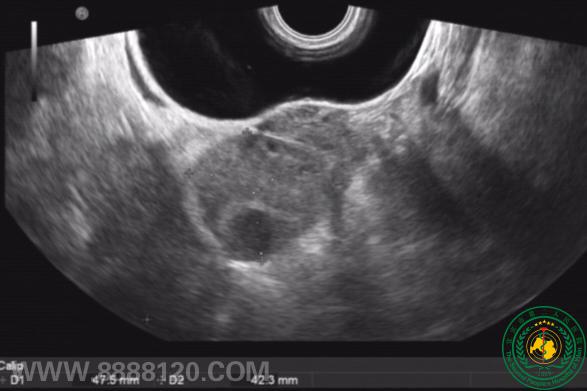

活泼过头的附件  52428

宜宾市第二人民医院 图文